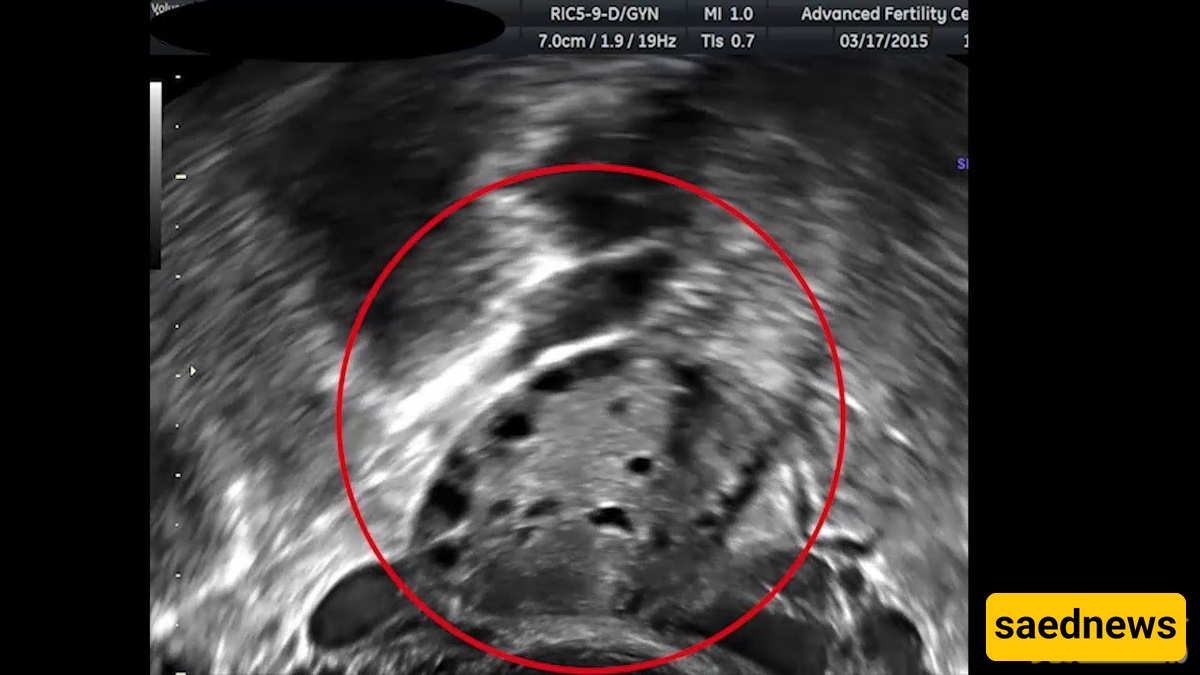

صوره موجات فوق صوتیه رائعه لقرده حامل

ساعدنیوز: الموجات فوق الصوتیه تکشف جنین قرد حامل